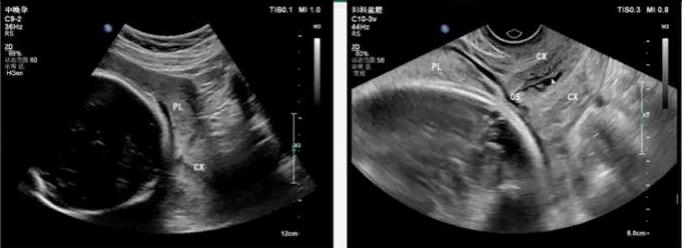

(1) 完全性前置胎盘:指孕28周后胎盘下缘完全覆盖宫颈内口(其中中央性前置胎盘是指胎盘中心部分覆盖在宫颈内口区域),横切面时,宫颈上方全部为胎盘回声。

(2) 部分性前置胎盘:胎盘组织部分覆盖宫颈内口。大多数超声检查前置胎盘时宫颈口尚未开张,而临床分类是在临产宫颈口开至3 cm以上第一次阴道检查时进行,因此不下部分性前置胎盘的超声诊断。

(3) 边缘性前置胎盘:是指孕28周后胎盘下缘达宫颈内口边缘(≤2 cm),但未覆盖宫颈内口。

(4) 低置胎盘(孕28周之前):胎盘下缘距宫颈内口≤2 cm。

(3) 经阴道超声是诊断前置胎盘的较好手段,可以弥补经腹部超声的不足。